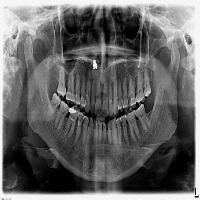

opg12 Computer Vision Project

ask

downloadsClasses (27)

ABCESS

ANKYOLISED TOOTH

ATTRITED TOOTH

BONE LOSS

BROKEN TOOTH

CARIES

CONDYLE

CROWN

CROWN AND BRIDGE

ERUPTING TOOTH

FRACTURE FURCATION INVOLVEMENT

GROSSLY DECAYED TOOTH

HARD PALATE

IMPACTED TOOTH

IMPLANT

INFERIOR ALVEOLAR NERVE CANAL

INFERIOR BORDER OF MANDIBLE

NERVE CANAL

RAMUS OF MANDIBLE

RESTORATION

ROOT CANAL BEYOND APEX

ROOT CANAL TREATED TOOTH

ROOT STUMP

SHORTENED RCT

VERTICAL BONE LOSS

maxillary sinus